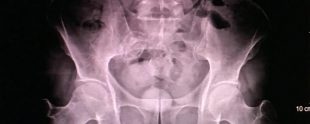

MAKATINDA GİZLEDİĞİ UYUŞTURUCUYU İSTANBUL’A GÖTÜRMEK İSTEYEN İRAN UYRUKLU KADIN NARKOTİK POLİSİNE YAKALANDI. KADININ TAŞIDIĞI UYUŞTURUCULAR...